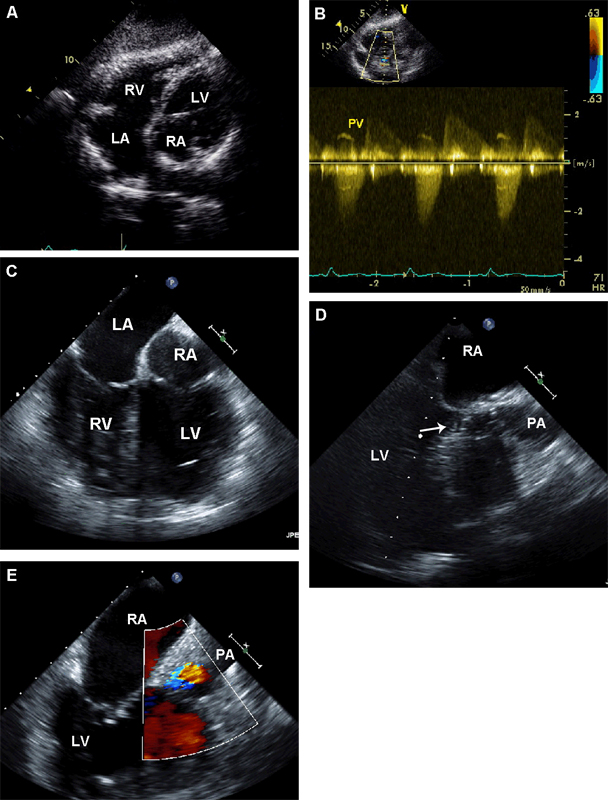

فحوصات تشخيصية لبعض امراض القلب والشرايين التاجية